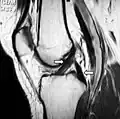

MRI of anterior cruciate ligament tear

An ACL tear is one of the most common knee injuries, with over 100,000 tears occurring annually in the US.[8] Most ACL tears are a result of a non-contact mechanism such as a sudden change in a direction causing the knee to rotate inward, placing additional strain on the ACL since the femur and tibia, which are the two bones that articulate together forming the knee joint, move in opposite directions, causing the ACL to tear. Most athletes require reconstructive surgery on the ACL, in which the torn or ruptured ACL is completely removed and replaced with a piece of tendon or ligament tissue from the patient (autograft) or from a donor (allograft).[9] Conservative treatment has poor outcomes in ACL injury, since the ACL is unable to form a fibrous clot, as it receives most of its nutrients from synovial fluid; this washes away the reparative cells, making the formation of fibrous tissue difficult.